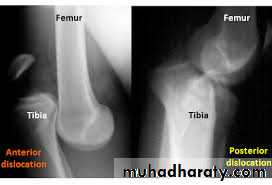

Knee dislocation

The knee can be dislocated only by considerable violence, as in a road accident.

The cruciate ligaments

and one or both lateral ligaments are torn.

There is sever swelling ,

bruises

and knee deformity.

The circulation and sensation in foot must be examined

to exclude popliteal vessels and nerve injuries

URGENT reduction by closed or open reduction

followed by

splinting the knee in 15 degrees flexion for 12 weeks and

physiotherapy.